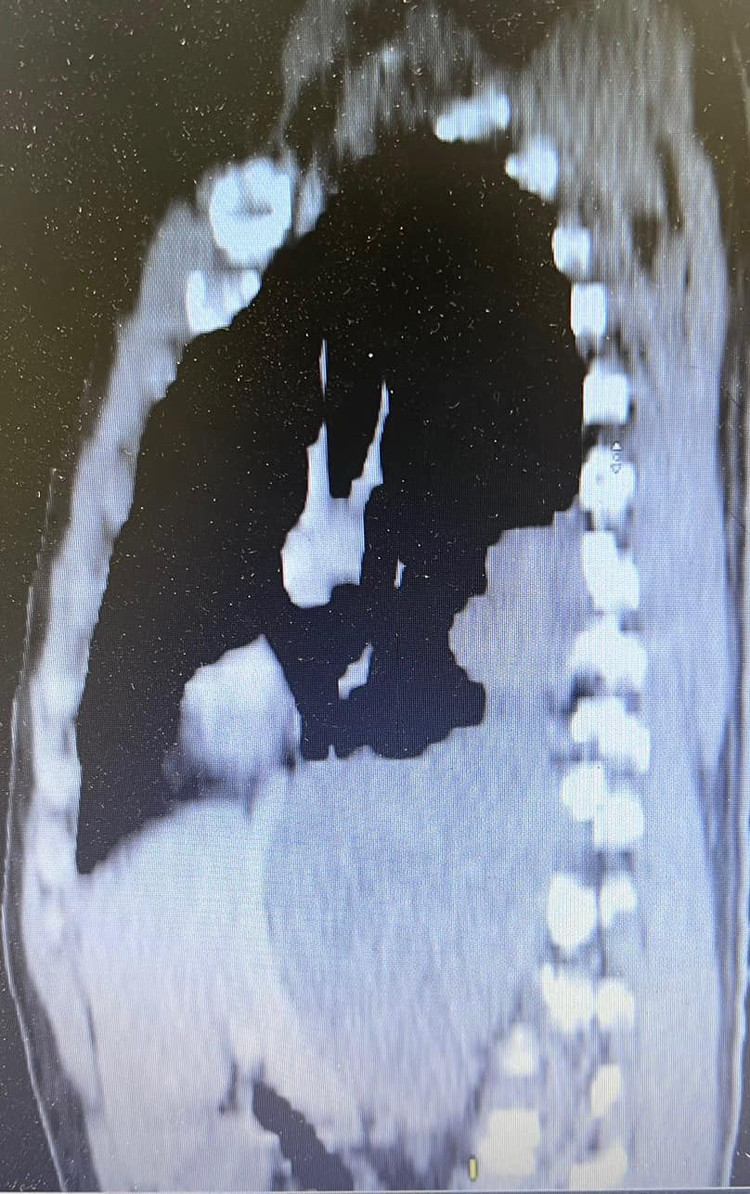

Bệnh nhân Nguyễn Hữu P. 43 tuổi, trú tại Hà Tĩnh được gia đình đưa đi khám tại Bệnh viện K Tân Triều vì đau tức ngực và bụng nhiều ngày. Qua thăm khám và chụp cắt lớp vi tính, các bác sỹ xác định bệnh nhân có khối u kích thước 15x20cm nằm ờ vùng trung thất sau lan xuống ổ bụng, cực trên u ngang mức D6-7, cực dưới u ngang mức động mạch thận phải, dính sát vào tĩnh mạch chủ dưới, động mạch chủ bụng và thùy dưới phổi phải. Kết quả giải phẫu bệnh của bệnh nhân P. là u schwannoma.

Bệnh nhân đã được chỉ định thuật thăm dò ổ bụng, trong quá trình phẫu thuật thăm dò đánh giá khối u nằm trên cơ hoành, đè đẩy cơ hoành và tĩnh mạch chủ dưới.

Đánh giá sau mở ngực, khối u choán toàn bộ phẫu trường, dính chặt vào thành ngực sau bên, cực trên u dính vào thùy dưới phổi phải, u nằm trên và đè đẩy cơ hoành, rất khó đánh giá mặt trong và cực dưới của u.